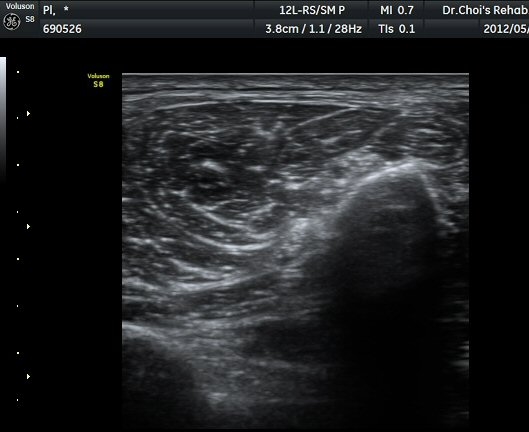

ŽÃËÀÚ¸¦ ¾Æ·¡·Î À̵¿ÇÏ¿© ºñ°ñµÎ ºÎÀ§±îÁö ÃѺñ°ñ½Å°æÀÇ ÁÖÇàÀ» µû¶ó ½Å°æÀ» È®ÀÎÇÏ¿´´Ù(±×¸² 3, 4).